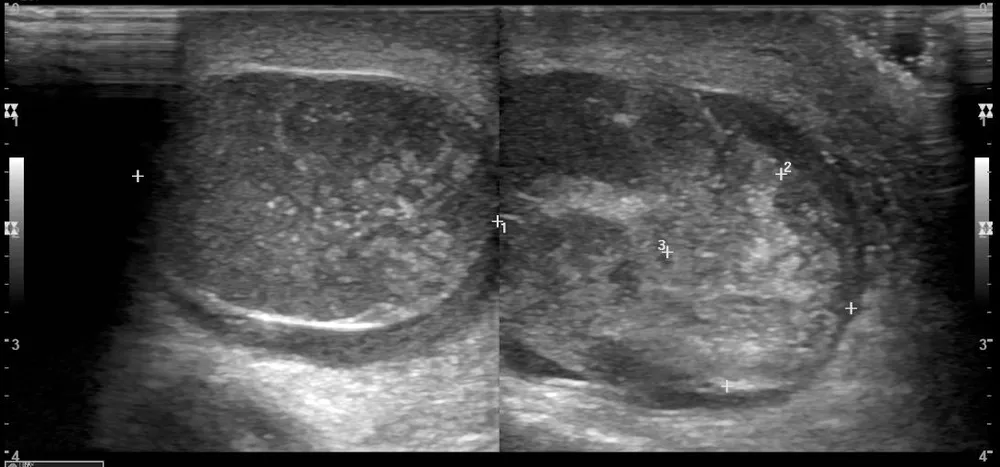

Do nhập viện muộn, qua siêu âm, xét nghiệm thấy tinh hoàn bắt đầu có dấu hiệu hoại tử, bệnh nhân được chỉ định mổ cấp cứu. Nhưng tinh hoàn trái có tổn thương tiên lượng không hồi phục, buộc phải cắt bỏ.

Đến khi đi khám thì tinh hoàn đã bắt đầu có dấu hiệu hoại tử trên siêu âm và xét nghiệm. Ảnh: BSCC |